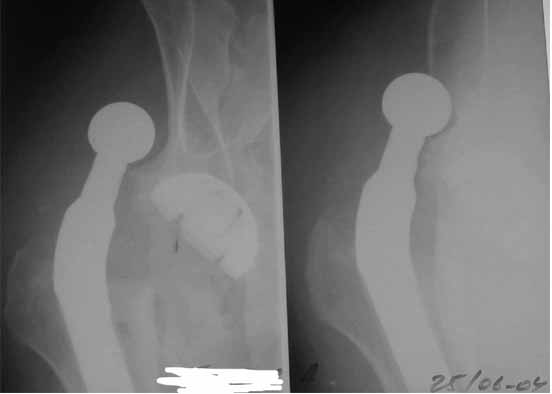

Re: вывих головки эндопротеза

Сан Саныч,

Консультировать вывихи по рентгенограммам, не зная хода операции, дело не очень благодарное. Я думаю, что с датой операции Вы ошиблись и это был 2004 год? Тем не менее. Настораживают два фактора. Первое - не видно большого вертела. Если с мышцами обошлись грубо и их отсекли, то это очень грустно и нужна "связанная" пара, т.н. "constrain cup". Смущает хорошо прослеживаемый малый вертел и небольшая ретроверсия чашки. Возможно это (избыточная ретроверсия ножки и чашки) могло послужить причиной вывиха. Обычно гипсовая повязка после операции не накладывается, значит, были глубокие сомнения у оперировавшего хирурга. В этом случае - ревизия с перестановкой как минимум - ножки, а как максимум - обоих компонентов.

Но желательно бы знать ход операции.

Во вложении - рентгенограммы после вывиха и после вправления.